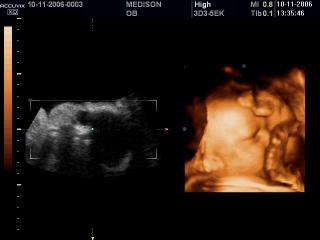

Лицо плода и пуповина, 3D

Accuvix-XQ. Лицо плода и пуповина, 3D.